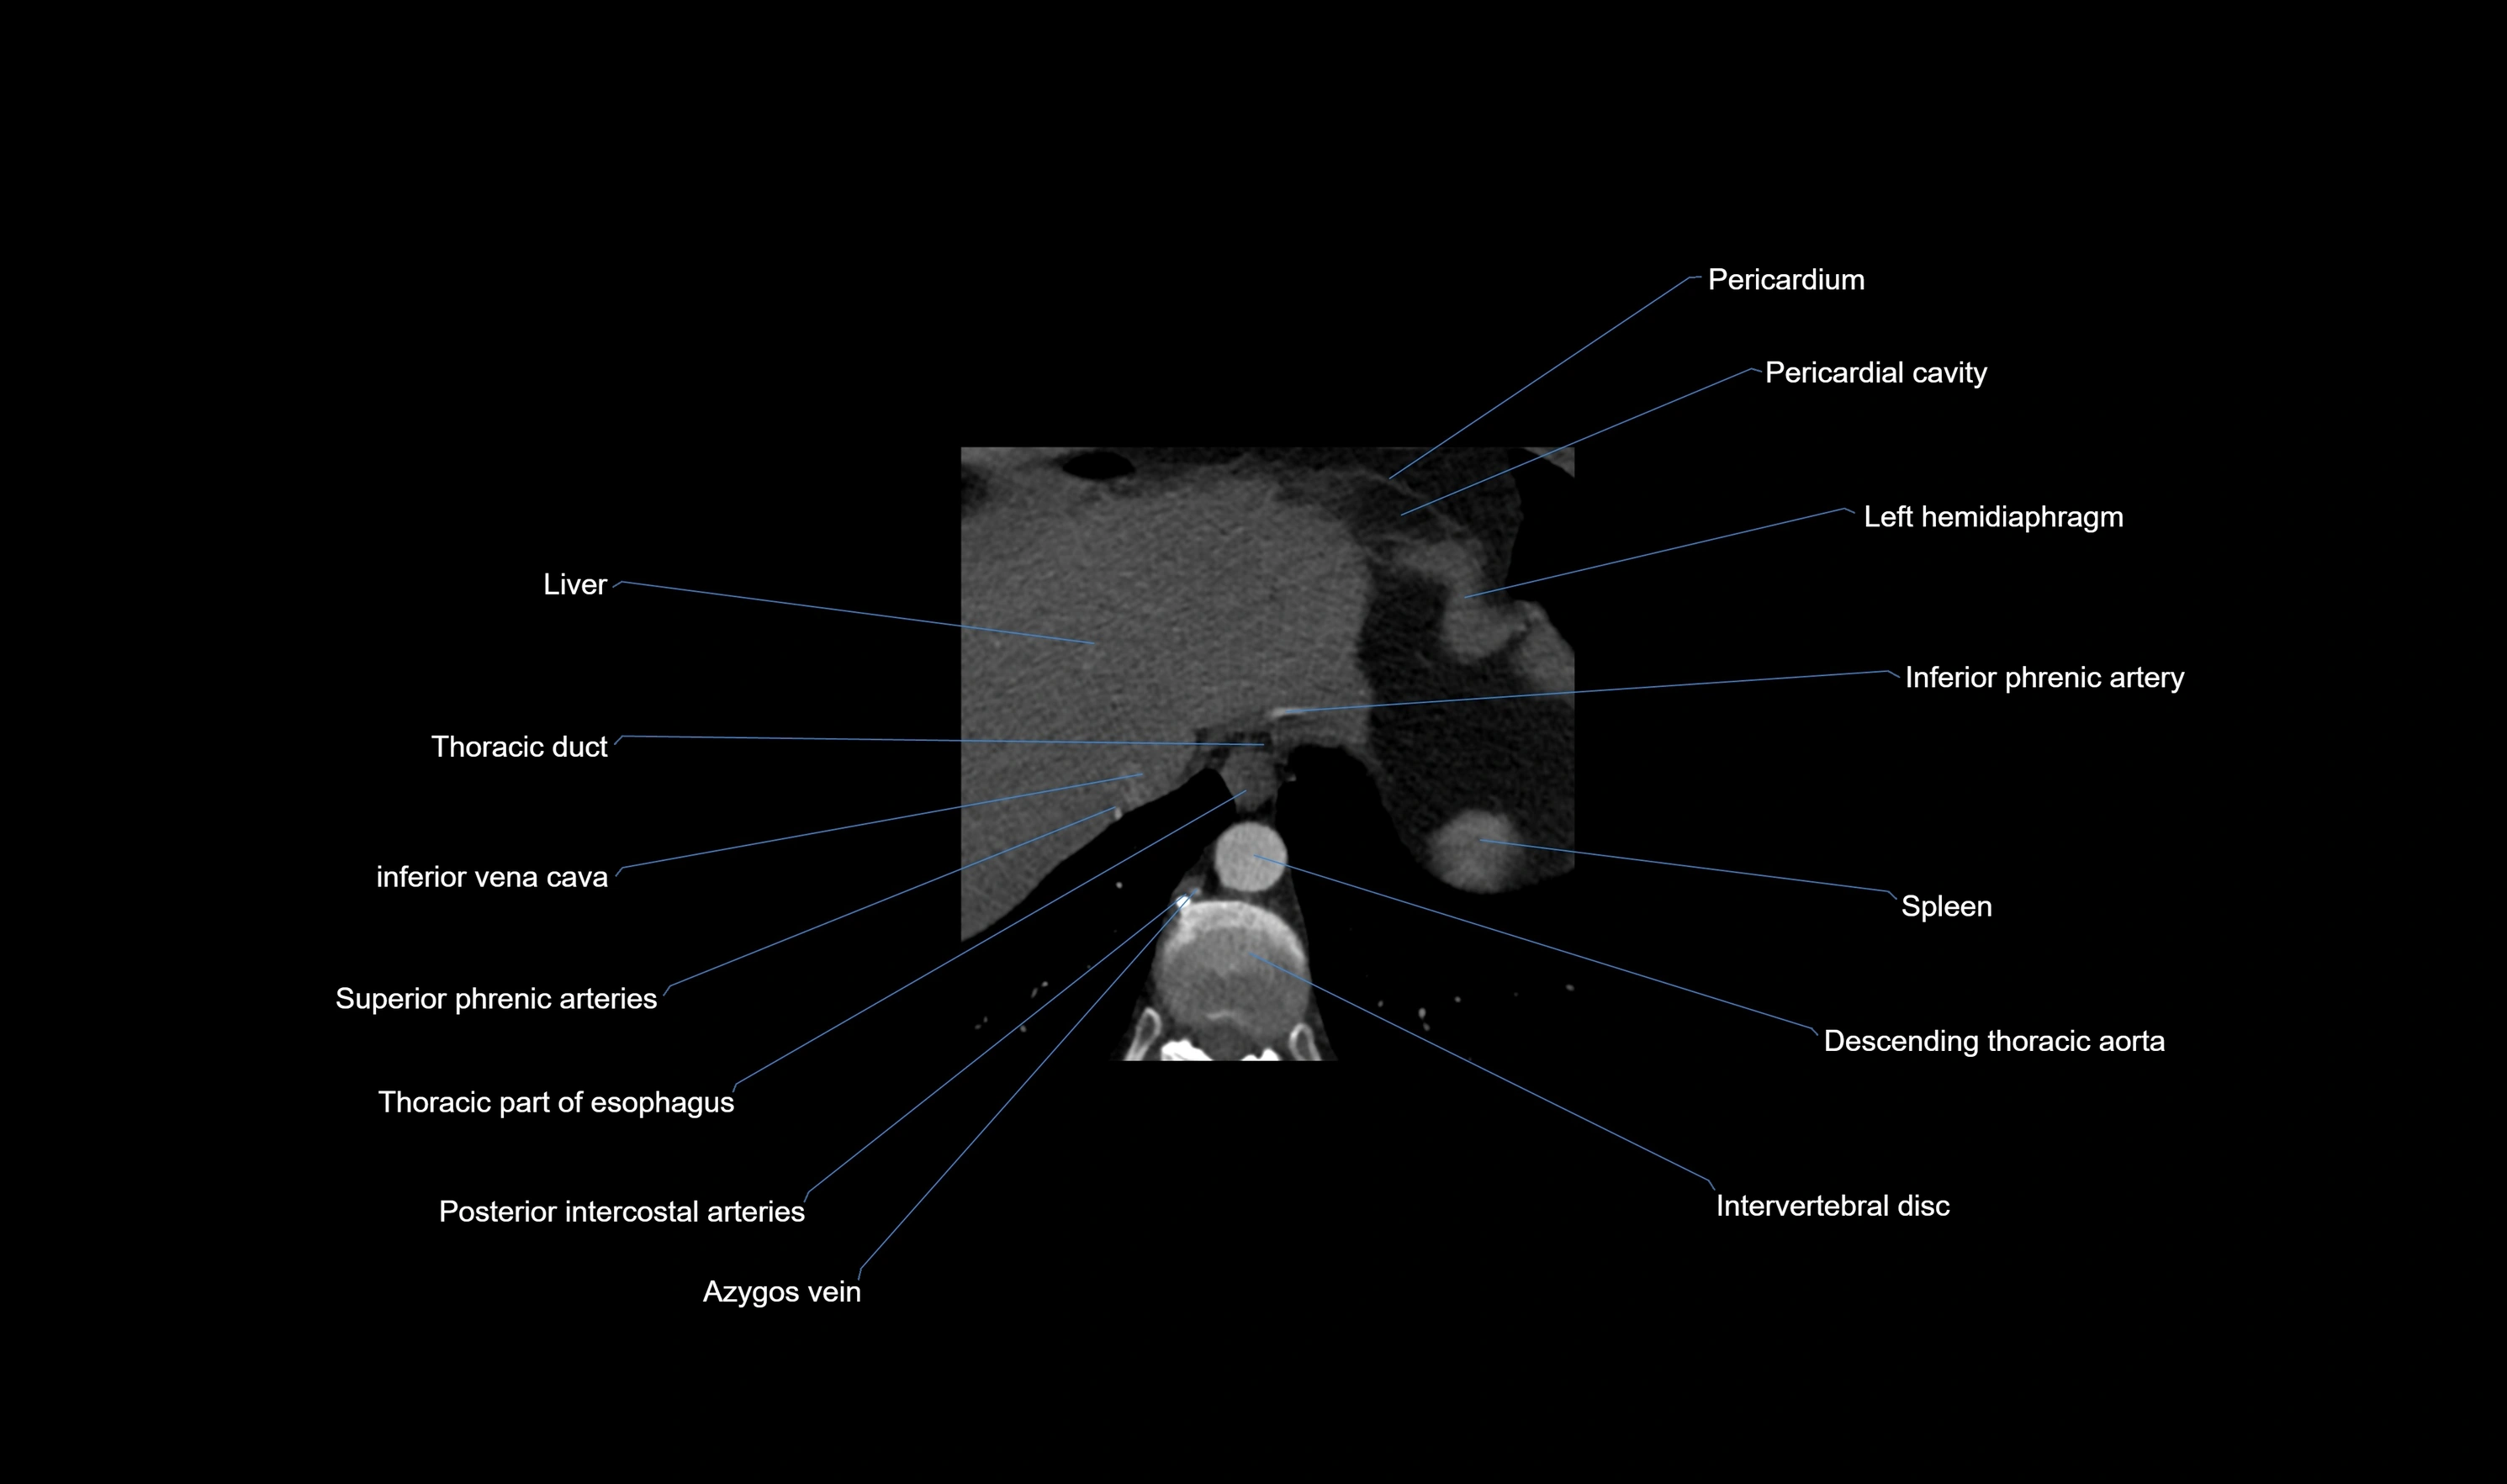

- Inferior phrenic artery

- Inferior vena cava

- Left hemidiaphragm

- Spleen

- Thoracic duct

- Transverse pericardial sinus

- Azygos vein

- Diaphragm